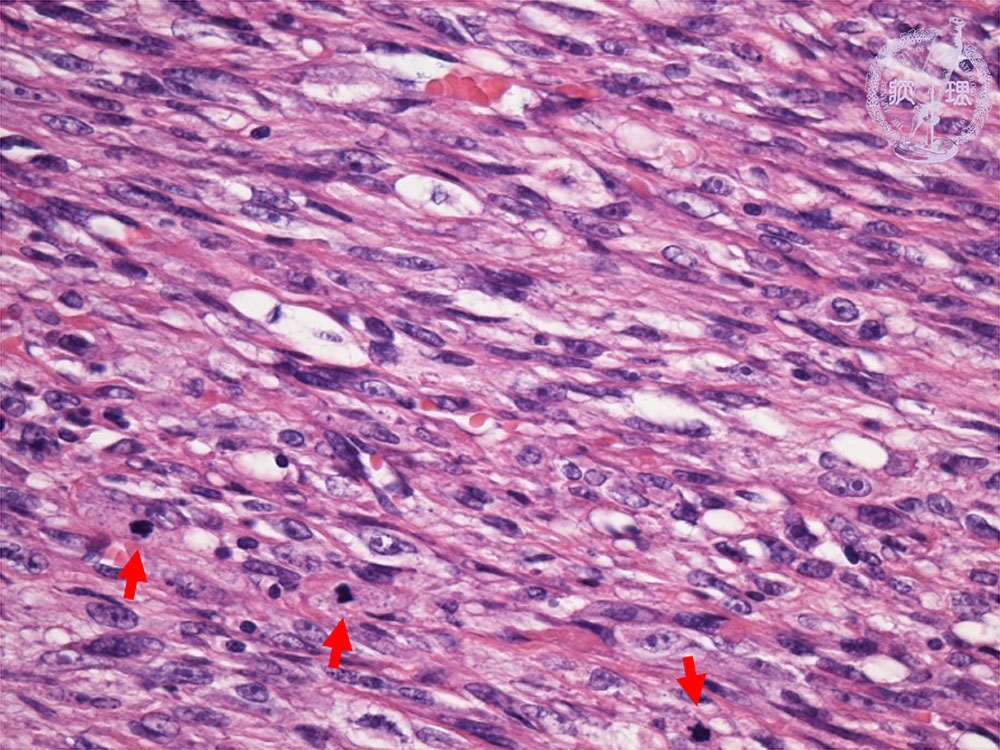

- ★(3)leiomyosarcoma

Histology (HE stain, high power): Higher nuclear density, larger nuclei, more irregular nuclei and mitotic figures compared to leiomyoma,